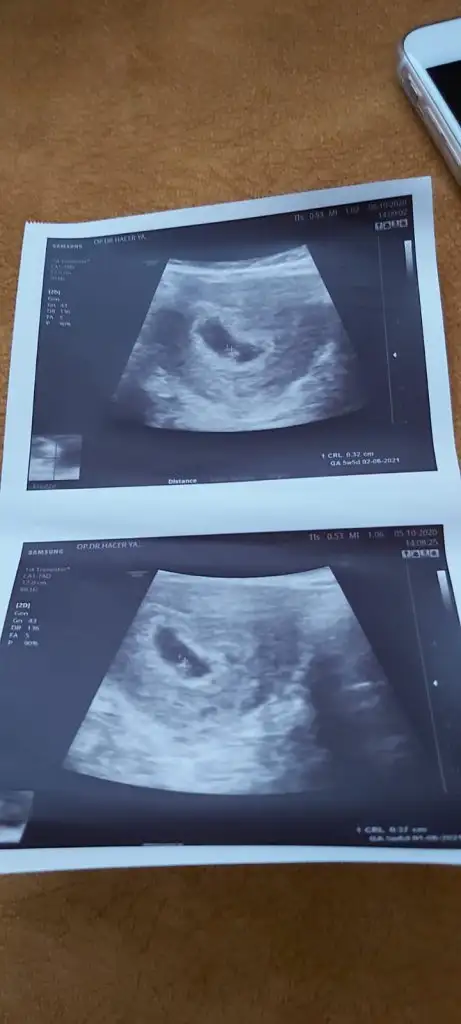

Merhaba bir kızım var ilk foto 6haftalık usg de kesesi yuvarlaktı 0.45 cm bu şekil

Şimdi ikinci gebeliğim ve cinsiyetim henüz belli değil yine 6haftalık usg fotomuz daha yayvan uzun 0.86cm